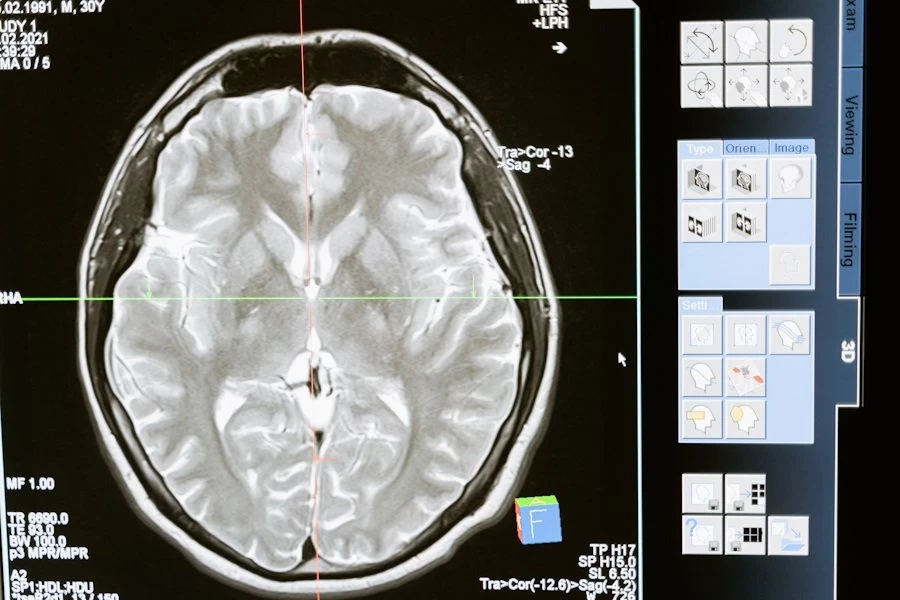

Исследование учёных из Медицинской школы Гроссмана Нью-Йоркского университета и 25 больниц выявило удивительные детали о работе мозга после остановки сердца. Оказалось, что у некоторых пациентов, реанимированных с помощью сердечно-легочной реанимации (СЛР), спустя час и более сохранялись четкие воспоминания, а мозговая активность демонстрировала паттерны, связанные с высшими психическими функциями, такими как память и осознание.

Согласно изданию NYULangone, в рамках исследования AWARE-II, проведённого с 2017 по 2020 год в США и Великобритании, изучались 567 пациентов, переживших остановку сердца. Менее 10% из них удалось стабилизировать настолько, чтобы выписать из больницы, однако 40% выживших вспомнили состояние сознания, возникшее во время СЛР. У 85 из этих пациентов была зафиксирована мозговая активность с использованием электроэнцефалограммы (ЭЭГ), которая продемонстрировала пики в гамма-, дельта-, тета-, альфа- и бета-волнах — все они связаны с когнитивными функциями.